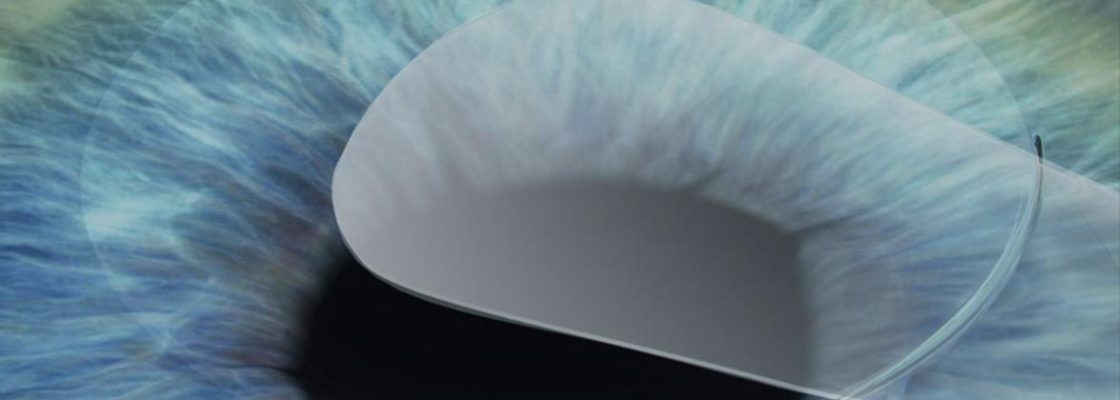

- Criação da lentícula corneano: o laser cria uma fina camada interna na córnea, chamada lentículo.

- Microincisão: é feita uma abertura de apenas 2 a 4 mm (bem menor que no LASIK, que chega a 20 mm).

- Remoção do lentículo: através da microincisão, o lentículo é retirado, alterando a curvatura da córnea e corrigindo o erro refrativo.